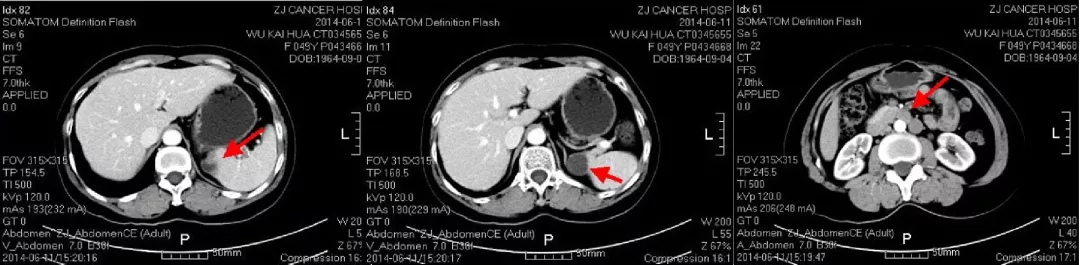

2021.5.8 PET-CT:肝肾隐窝转移灶。2021.5.12复查CA125水平为95.5U/ml。

PET-CT检查结果